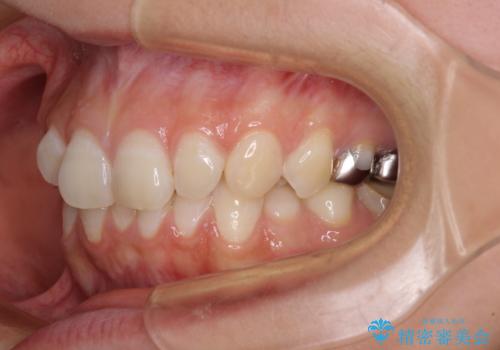

- 下顎の前歯が隠れていることと、デコボコを気にして来院された患者様です。

目立ちにくい装置を希望されていたため、ワイヤー装置とインビザラインを提案したところ、インビザラインを希望されました。

銀歯やムシ歯処置の必要な歯が奥歯にあり気になっていたので、矯正治療の途中でセラミッククラウンへ変更し、その後歯列を仕上げていくこととしました。